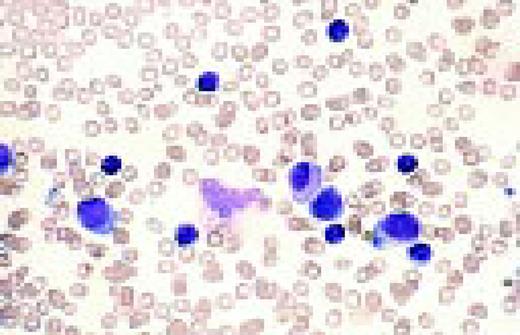

Slide L35

Burkitt's lymphoma. Composite: bone marrow biopsy (L) and bone marrow aspirate (R). Giemsa stained. This 19-year-old male presented with a submandibular tumor in 1997. A biopsy revealed non-Hodgkin's lymphoma, Burkitt's type, according to the REAL classification. Staging revealed stage I disease. He was treated with aggressive polychemotherapy for Burkitt's lymphoma and an allogeneic bone marrow transplant was planned for March 1998. Two weeks before BMT, the patient complained of back pain, and there was a sharp rise of LDH. A bone marrow smear and biopsy revealed massive infiltration by Burkitt lymphoma blasts. Few tumor cells were seen in the blood smear. The slide (R) shows typical Burkitt's lymphoma with vacuolated cytoplasm (ALL-L3 blasts according to the FAB classification). The bone marrow biopsy (L) also shows the typical, leukemia type, interstitial infiltration, leaving the fat cells intact.FIG35